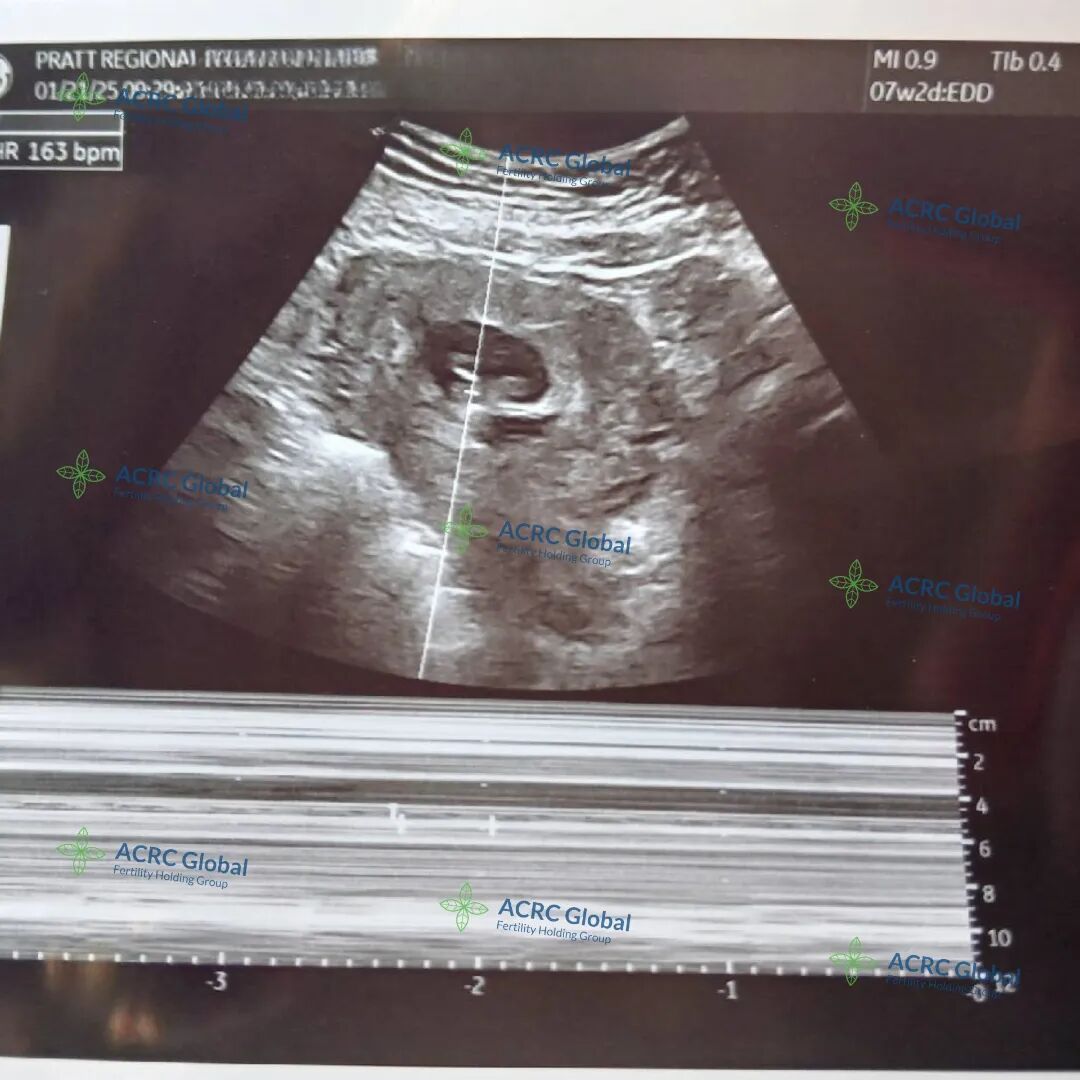

爱妈D的首次胎心监测来了!宝宝现在才7周零两天,虽然小得像一颗蓝莓,但这个小小的生命已经跳动出了有力的心跳声💓小小的你是全家的希望,满怀信心地期待着你从诊所“毕业”!